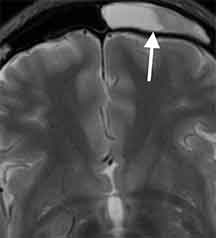

24歳男性、両側の目の奥の痛みで受診。頭部MRI検査で篩骨洞の炎症を認めました。